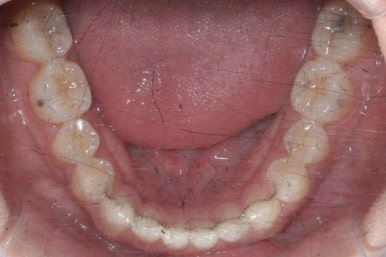

부산치아교정치과에서 치료한 이 사이가 벌어진 틈새교정을 마무리 했을 때의 모습을 보여드리겠습니다.

몰라보게 바뀌었습니다.

틈새가 다 모였고 다시 틈이 벌어지지 말라고 앞니 안쪽에는 유지장치를 달고 마무리를 했습니다.

전후를 비교해 보겠습니다.

부산치아교정치과 전후 모습입니다.

변화가 놀랍습니다.